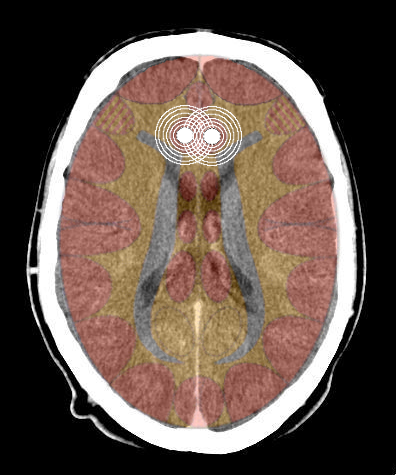

- Requisiti: Si è in costellazione schizofrenica quando due attivazioni colpiscono i due emisferi cerebrali di uno stesso livello:

- le due emiparti del tronco cerebrale;

- i due emisferi cerebellari;

- i due emisferi cerebrali (midollo e/o corteccia).

- NON È COSTELLAZIONE quando due attivazioni interessano due livelli cerebrali differenti, anche se occupano i due emisferi.

Possono esserci due o più costellazioni schizofreniche anche su livelli differenti (ad es. una costellazione corticale e una cerebellare) - I relè cerebrali: In una costellazione si possono avere: